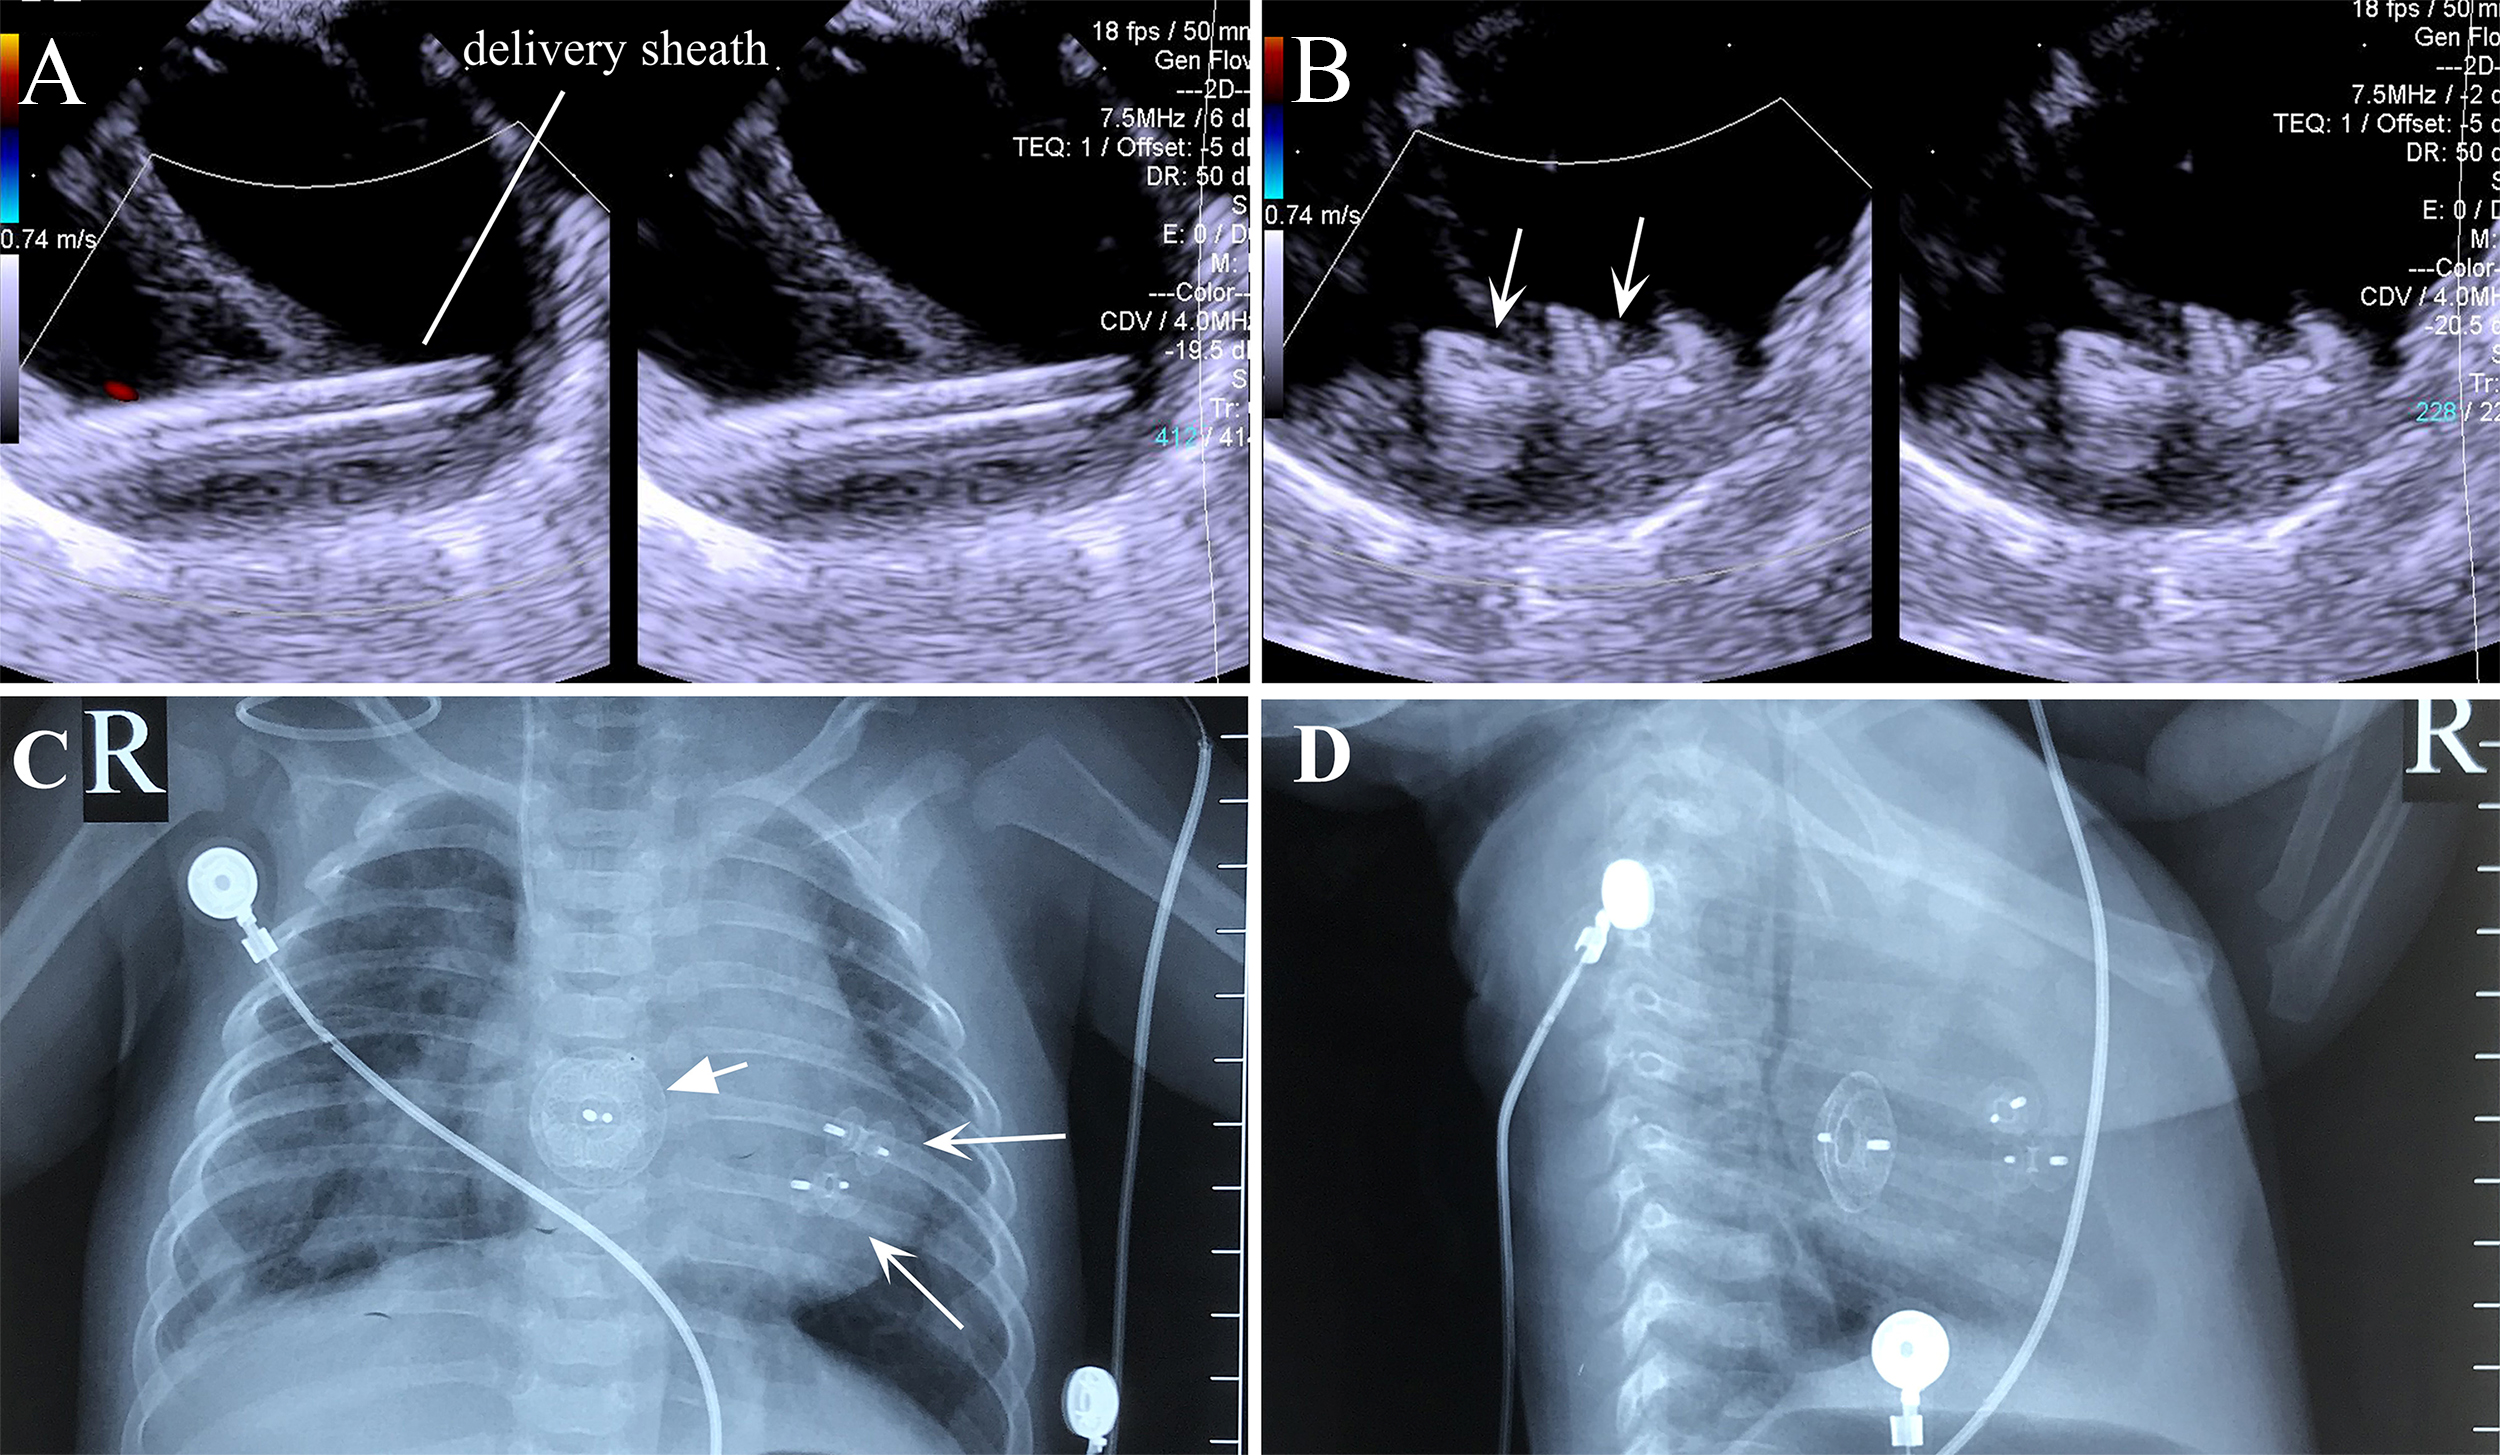

Two occluders were used during surgery on one patient with apical multiple mVSDs (three holes): a 6 mm waist-diameter muscular occluder was used to close the “middle hole”; meanwhile, the “lower hole” was closed by squeezing the occluder on the atrial septum. However, due to the wide defect spacing and TEE showing a significant shunt in the “upper hole”, a 5 mm waist-diameter muscular occluder was subsequently used to close the “upper hole” (Fig. 6).

Fig. 6. Transesophageal echocardiography and X-ray images of the combined lower mini-sternotomy perventricular approach for treating multiple mVSDs combined with a percutaneous approach for treating ASD. (A) Delivery sheath passing through apical mVSD. (B) Successful occlusion of multiple apical mVSDs using two VSD occluders. (C) Postoperative chest frontal view showing two VSD occluders and one ASD occluder. (D) The chest lateral view shows two VSD occluders and one ASD occluder. Note: arrow = occluder.